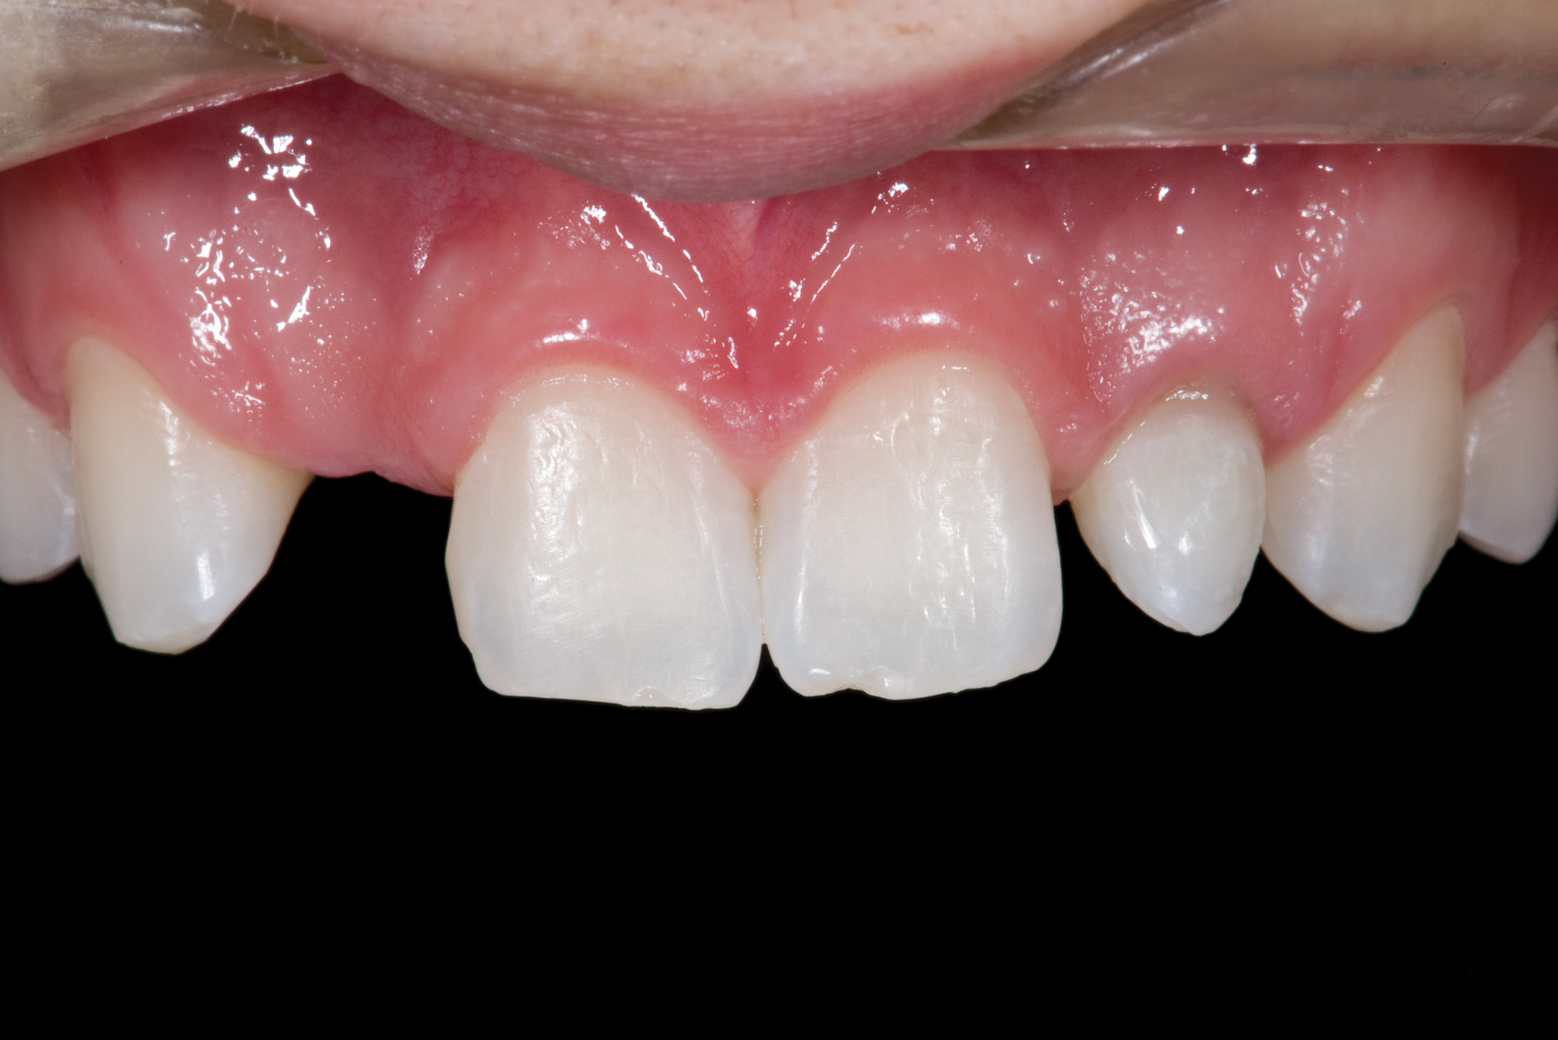

Fig 13. Deficient ridges in the areas of the missing lateral incisors.

Figure 13